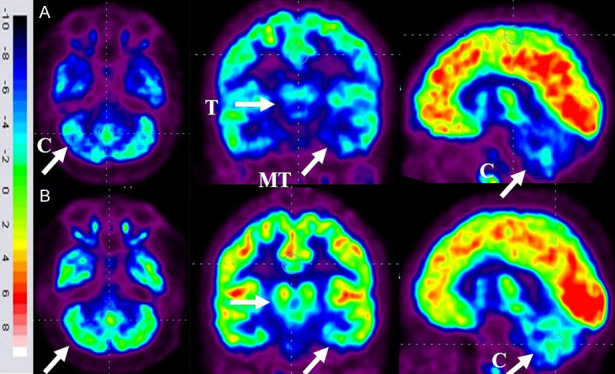

86名患者的家長同意在干預6個月后重復進行FDG-PET CT掃描以進行比較分析。干預前,這些患者的FDG-PET/CT掃描顯示雙側內側顳葉皮層、丘腦和小腦的代謝活動降低[代謝減退]。此外,它們還表現出尾狀頭、殼核、眶額皮質和前額葉皮質的代謝活動增加(代謝亢進)。

干細胞移植六個月后,所有患者的大腦活動均得到改善。此前,代謝低下區域[內側顳葉皮質、丘腦和小腦]顯示FDG攝取增加,而代謝亢進區域[尾狀頭、殼核、眶額皮質和前額葉皮質]顯示FDG攝取減少(圖6)。在進行T檢驗時,發現干預前后這些區域的平均SUV出現了統計學上的顯著變化[P<0.05]。

A.頂行:標有箭頭的藍色區域表明代謝低下。B. 下排:用箭頭標記的綠色區域表明細胞移植后新陳代謝得到改善。

客觀神經影像學

FDG PET CT大腦掃描被用作接受多劑量細胞移植的患者的額外結果測量。它用于監測細胞水平干預的效果。這種功能性神經影像技術利用18-FDG來研究大腦的代謝活動。我們對86名患者進行了FDG PET CT掃描腦部的比較研究,結果證明了其對新陳代謝的平衡作用。代謝低下的區域顯示代謝增加,而代謝亢進的區域顯示代謝減少。